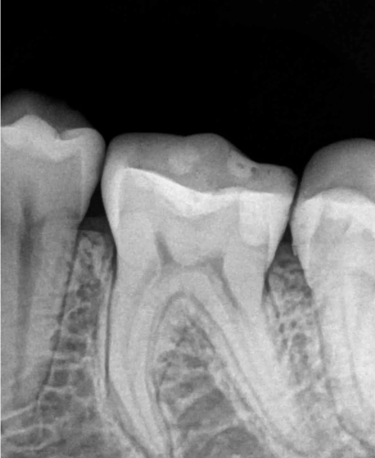

RTG punktowe to jedno z podstawowych badań radiologicznych w stomatologii, umożliwiające dokładną ocenę pojedynczego zęba oraz otaczających go struktur. Badanie pozwala wykryć próchnicę, ocenić stan korzeni, kanałów zębowych oraz tkanek okołowierzchołkowych.

W naszej pracowni RTG stomatologicznego w Gdyni wykonujemy zdjęcia punktowe, które stanowią niezastąpione wsparcie w leczeniu kanałowym, diagnostyce stanów zapalnych i urazów zębów. Badanie jest szybkie, bezpieczne i precyzyjne, zapewniając lekarzowi pełne informacje potrzebne do skutecznego planowania leczenia.